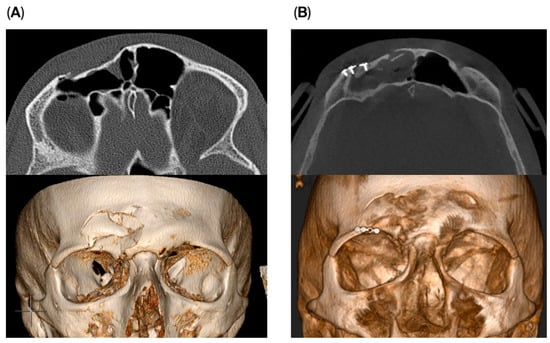

Osteosynthesis material was used in two cases within the endoscopic transorbital group to reconstruct the supraorbital rim and for stabilization of the fracture fragments. A small 1.5 plate was used to stabilize the fragments with fixation on the supra-orbital rim (Figure 4). The remaining four patients did not require osteosynthesis material. No impact on outcome was seen if osteosynthesis was used or not.

Figure 4. Pre- (A) and postoperative (B) images of a patient receiving the endoscopic transorbital approach with the use of osteosynthesis material for stabilization.